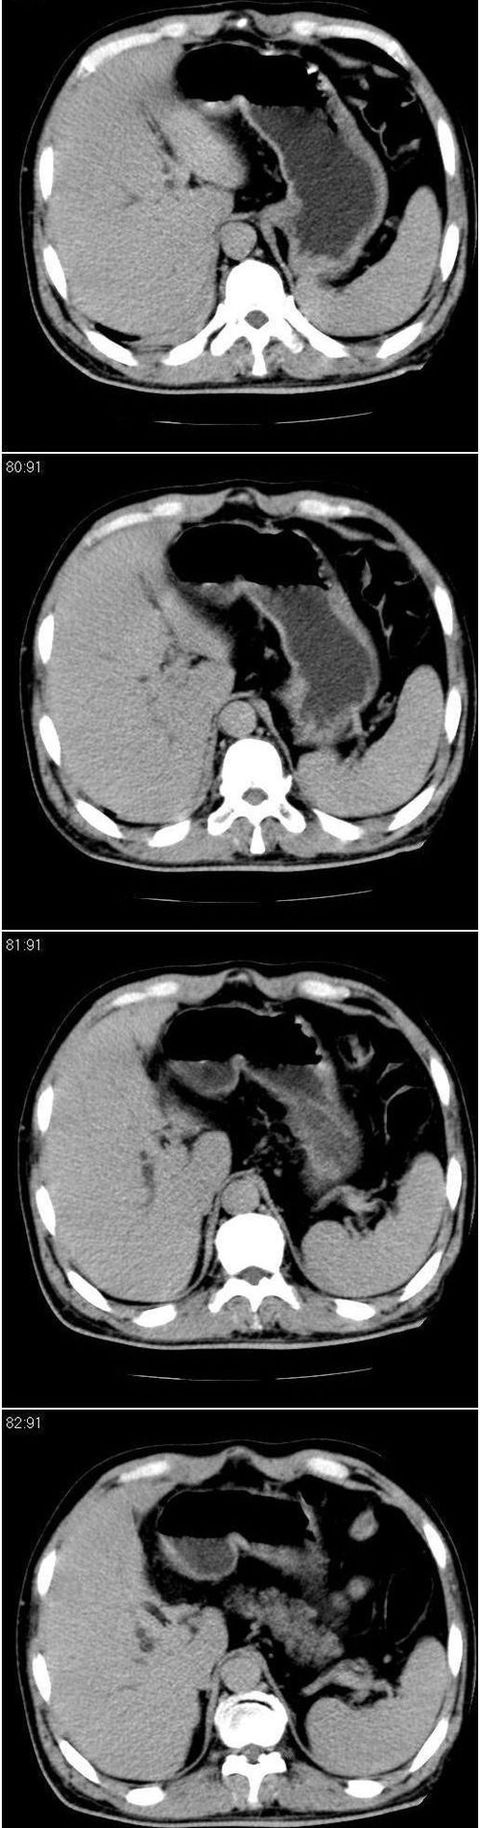

男,57岁。因胆结石阻塞性黄疸入院。这是胆囊切除术后的照片,看看此片到底有什么问题。

肝内外胆管轻度扩张,胆囊窝内见引流管考虑胆囊切除术后改变.胃窦部软组织似增厚,建议胃镜检查.

在手术切除胆囊的过程中,发现肝门部胆总管恶性占位,因为家属不同意手术,没有切除,能看出来么?

不是楼主提醒还真看不出来,肝内胆管扩张。略显僵硬。

肝内外胆管轻度扩张。楼主提示左右肝管合汇区域壁稍厚。胆总管末段壁似也稍厚有轻度强化。就现有资料诊断难。